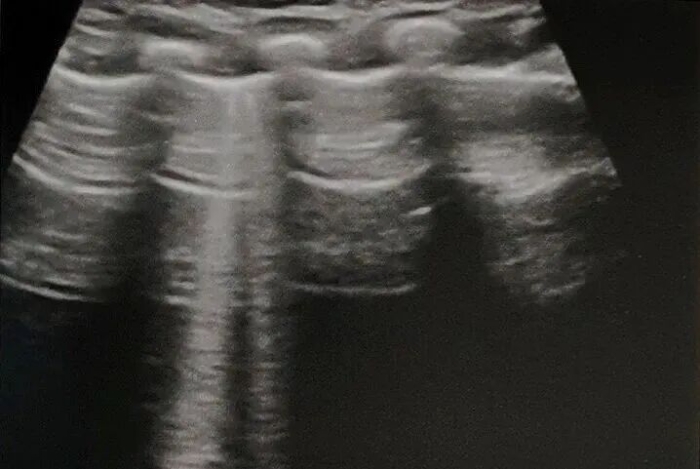

沙滩征: 是由脏胸膜以及肺组织随呼吸相对于壁胸膜及胸壁的运动所形成,产生机制同肺滑动征。

气胸: 通过观察肺滑动征是否存在,是否有肺点,快速判断是否有气体跑到了胸腔里 。